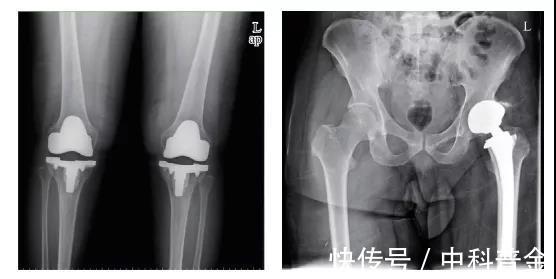

图1 植入人体中的金属关节

医用金属材料的应用历史非常久远。早在2000年前,古罗马人将熟铁用于制作假牙,中国人也将黄金用于牙齿修补。16世纪后,出现了将纯金薄片和铁丝分别用于颅骨缺损和断骨修复的文献记载。19世纪60年代,无菌手术技术出现后,铁、金、银等金属植入物开始得到大量应用(图1)。20世纪30年代以来,随着材料学和医学研究的快速发展,逐步开发和应用具有优异力学性能、耐蚀性能、加工性能和生物相容性的多种医用金属材料。目前,不锈钢、纯钛及钛合金、钴基合金成为医疗器械制造中使用的三大类医用金属材料。另外,形状记忆合金、金等贵金属,以及钽、铌、锆等稀有金属,也得到一定的临床应用(图2)。